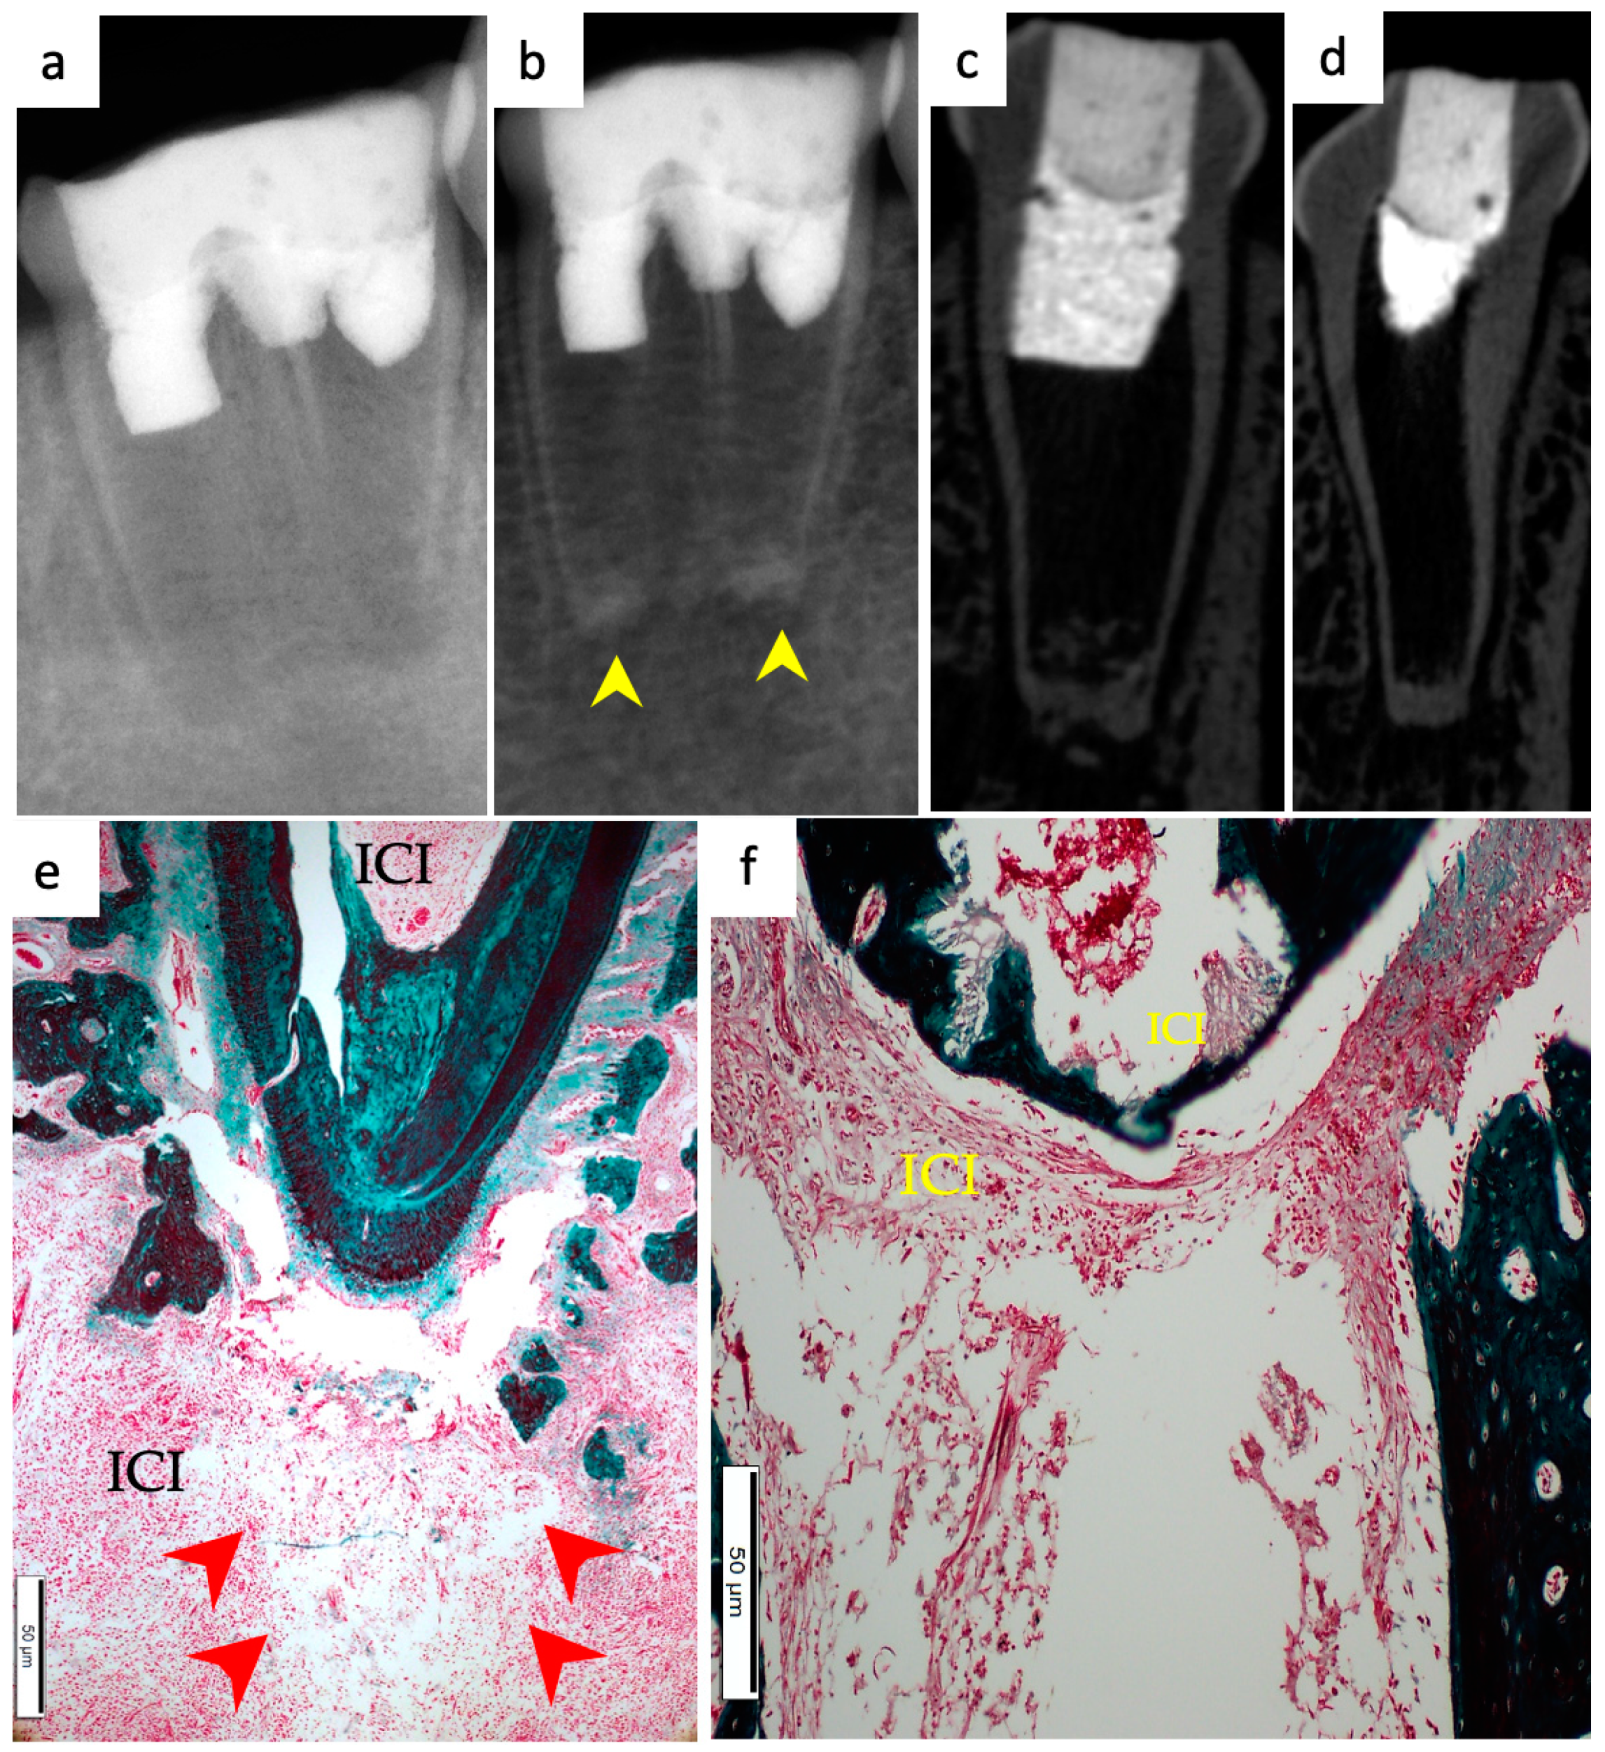

3.6. Positive and Negative Control Groups